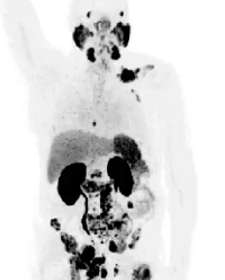

Interesting questions raised by a paper that compared the use of 18F-fluciclovine with 68Ga-PSMA-11 imaging modalities to detect biochemical relapse in prostate cancer and implications for integrating newer techniques into clinical practice.

Reactions to key findings from an article by Birgit Pernthaler, et al, that compared the use of 18F-fluciclovine with 68Ga-PSMA-11 imaging modalities to detect biochemical relapse in prostate cancer.

Drs Steven Finkelstein and Louis J. Mazzarelli highlight data revealed in the article “A Prospective Head-to-Head Comparison of 18F-Fluciclovine With 68Ga-PSMA-11 in Biochemical Recurrence of Prostate Cancer in PET/CT,” by Birgit Pernthaler, et al.

Drs Steven Finkelstein and Louis J. Mazzarelli comment on limitations associated with conventional imaging modalities in prostate cancer and highlight the roles of newer tests such as 18F-fluciclovine and 68Ga-PSMA-11.